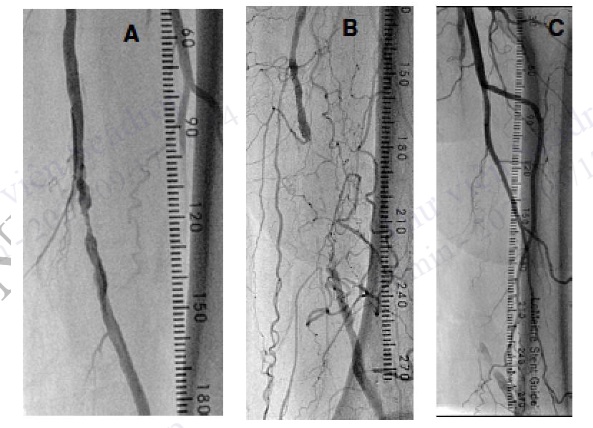

Hình 4.103. Dùng thước đo đánh giá chiều dài tổn thương. A: Hẹp trên đoạn dài 3 mm, B: Tắc hoàn toàn trên đoạn dài 7 cm, C: Tắc hoàn toàn trên đoạn dài 16 cm